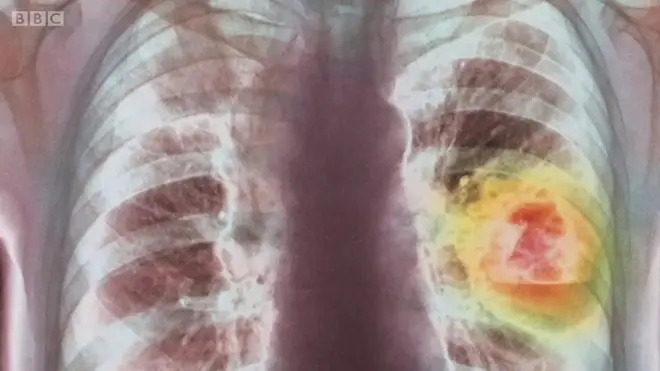

El cáncer visto desde dentro.

Eso es lo que permite un modelo tridimensional de tumor que se puede explorar mediante la tecnología de realidad virtual.

Fuente de la imagen, Getty Images